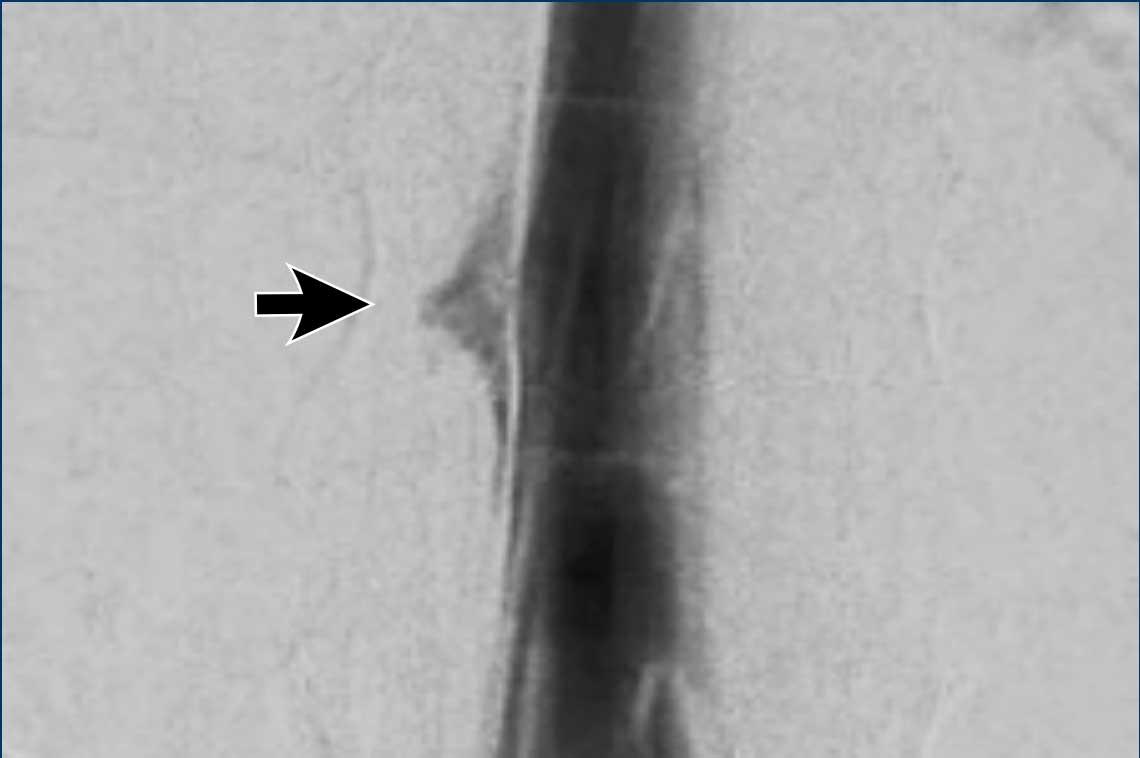

Cuối cùng, chụp tủy đồ xóa nền kỹ thuật số (digital subtraction myelography) được thực hiện (Courtesy René van den Berg).

Đầu tiên, tiến hành chọc dò thắt lưng.

Sau đó, bệnh nhân được đặt nằm nghiêng một bên và chụp ảnh với chùm tia nằm ngang trong khi thuốc cản quang được bơm vào và di chuyển theo hướng lên trên (xem video).

Khi bệnh nhân nằm nghiêng trái, không thấy bất thường nào.

Video này được ghi lại khi bệnh nhân nằm nghiêng phải.

Câu hỏi

Bạn có thấy rò dịch não tủy nào không?

Tiếp tục với các hình ảnh tiếp theo…

Ở mức ngực thấp, có hiện tượng rò thuốc cản quang qua một rò dịch não tủy – tĩnh mạch.

Trong quá trình phẫu thuật, các đám rối tĩnh mạch nổi bật đã được đốt điện và rễ thần kinh Th8 được thắt lại.